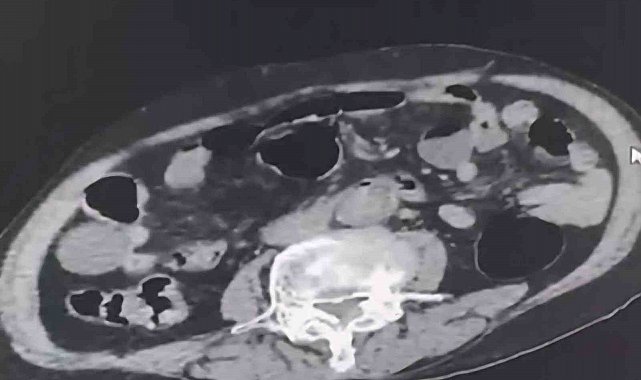

Denizli İl Emniyet Müdürlüğü Narkotik Suçlarla Mücadele Şube Müdürlüğü tarafından uyuşturucu madde ticaretinin önlenmesine yönelik yapılan çalışmalar kapsamında şehir dışından Denizli'ye uyuşturucu sokmak isteyen 2 yabancı uyruklu şahıs takibe takıldı. Takip sonrasında Denizli'de malları teslim edeceği kişi ile buluştukları esnada düzenlene operasyonla 3 şahıs gözaltına alındı. Gözaltına alınan şüpheliler üzerinde yapılan incelemelerde yabancı uyruklu bir şüphelinin uyuşturucu maddeyi cinsel organında taşıdığı belirlendi. Şüphelilerin üzerlerinde ve adreslerinden yapılan aramalarda 6 parça halinde 145 gram metamfetamin maddesi, 260 gram sıvı halde sentetik ecza maddesi ele geçirildi.